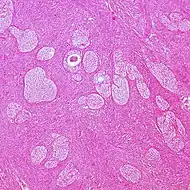

| Endometrioid tumor | 1% | Almost 100% | Tubular glands, resembling endometrium.[7] | ![]() | |